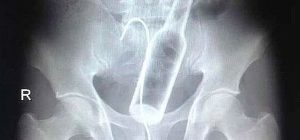

Malum Bölgelerine Kazayla Giren Nesnelerr

Röntgen görüntülerinde ortaya çıkan şaşırtıcı şeyler, hastane koridorlarında olanlar bilir…